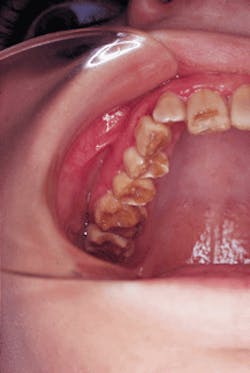

A 16-year-old male visited a dentist for an

initial examination. Oral examination revealed a generalized brown-colored dentition.

No unusual or abnormal findings were identified during the extraoral examination. Intraoral examination revealed a generalized brown-colored dentition (see photo). Examination of the oral soft tissues revealed no unusual findings and no bony abnormalities. Radiographic examination revealed teeth with thin amounts of enamel and areas where the enamel had fractured away (see radiograph).